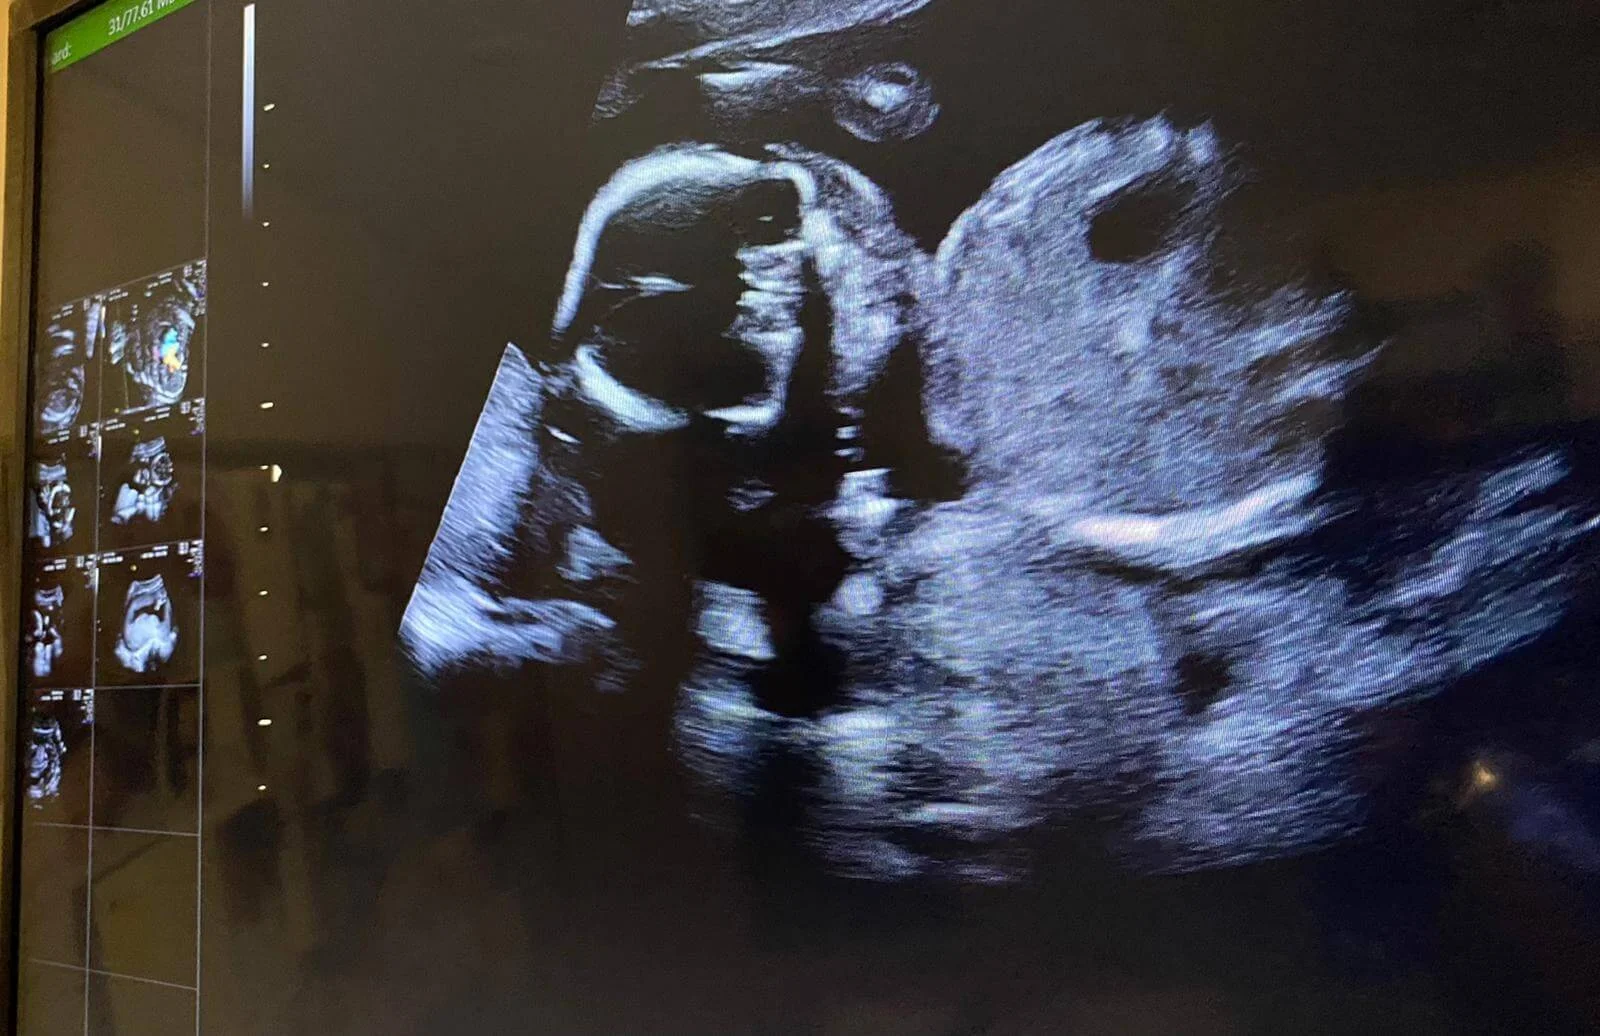

陪太太做產檢,看見腹中BB超聲波圖時,相當興奮。